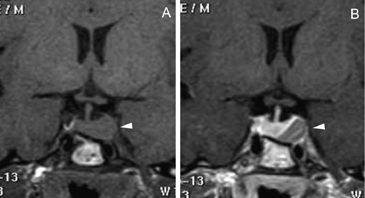

Figura 15 A, B y C. Cortes sagital T1w, coronal T1w Gad. y coronal T2w. Absceso pituitario que simula un macroadenoma quístico no funcionante.El compromiso del seno cavernoso (definido como la invasión perivascular de la arteria carotida interna), se observa en 19% de los macroadenomas y es habitualmente unilateral (Figuras 16A, 16B y 16C) pero puede ser bilateral en macroadenomas invasores (Figuras 17A y 17B). Para evaluar la invasión del seno cavernoso se utilizan las imágenes coronales T1w con gadolinio, efectuando el análisis de la forma y compartimientos del seno cavernoso y su relación con el adenoma; cuando el porcentaje de tumor que rodea la arteria carótida interna intracavernosa es mayor o igual a 66% del círculo medido alrededor de la carótida, hay invasión del seno, si es menor de 25%, el seno no está invadido48.

Figura 16A, B y C. Cortes coronales T1w sin y con Gadolinio y T2w. Macroadenoma con expansión asimétrica de la silla turca e invasión del seno cavernoso izquierdo.

Figura 17A y B. Cortes coronal y axial transversal, T1w Gad. Macroadenoma con crecimiento hacia lateral (entre puntas de flecha), mayor a derecha con invasión de ambos senos cavernosos; el quiasma está libre.Los adenomas invasores (Figuras 18 y 19) constituyen un grupo aparte y de acuerdo con series recientes publicadas representan entre 10% a 35% de los adenomas pituitarios operados49. En estos casos el potencial de invasión es estimado con mayor precisión con estudios histoquímicos y ultraestructurales de las muestras obtenidas durante la cirugía. Estos estudios patológicos, en conjunto con la cuantía de tumor residual demostrada con las neuroimágenes postoperatorias, definirán la conducta terapéutica a seguir.